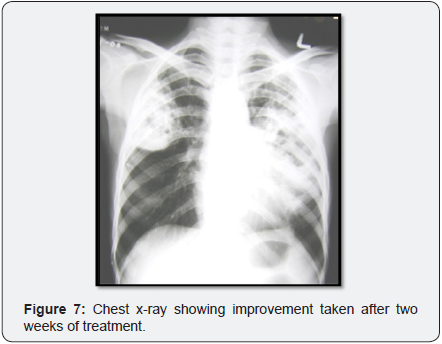

Expectorated sputa were positive on Gram staining for branching, beaded, filamentous bacteria (Figure 6) and negative on stain for Pneumocystis and AFB but later positive for modified acid-fast staining. The patient was continued on high dose oral Trimethoprim/sulfamethoxazole with continued clinical improvement and was discharged from the hospital on that regimen. Follow up X-ray showed improvement (Figure 7).